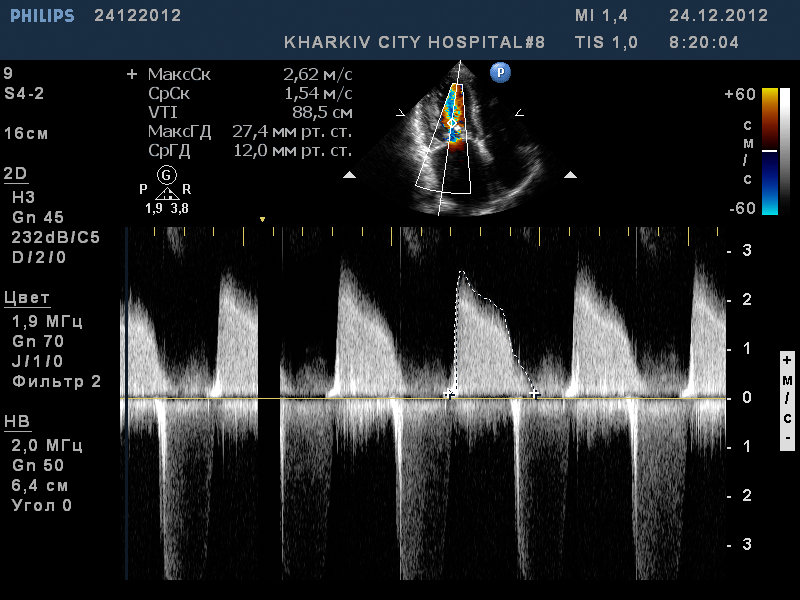

Пациент 52 лет. Поступил с нарушение ритма.

Заключение узи : склеротические изменения аорты, фиброзные изменения створок аортального клапана, незначительная недостаточность аортального клапана, частичный отрыв хорд передней створки митрального клапана, значительный митральный стеноз, умеренная МН, дилатация левого предсердия (6,0см), гипертрофия левого желудочка.